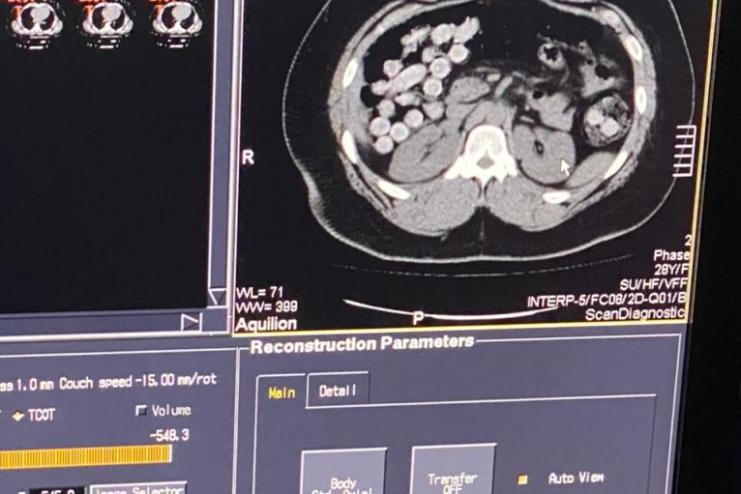

Всего правоохранители выявили кокаина общим весом 2 кг. Один из злоумышленников перевозил наркотики в личных вещах. Другой пытался перевезти через государственную границу свыше 1 кг кокаина в желудочно-кишечном тракте.